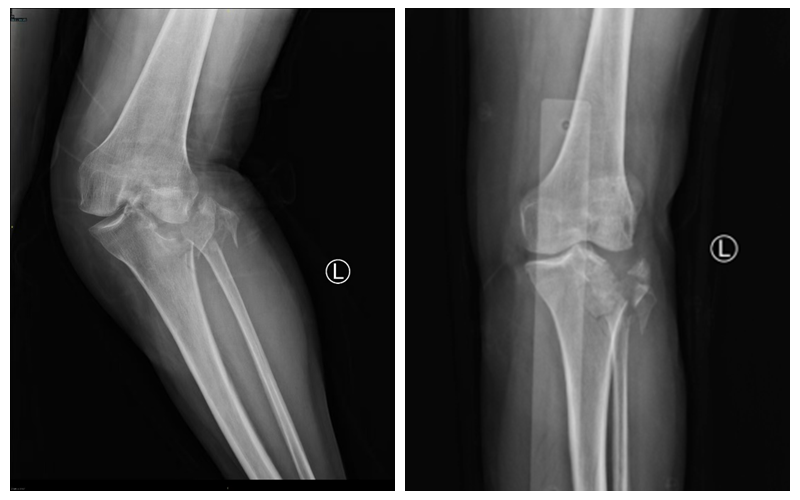

胫骨平台骨折的陷阱在于:X光片看到的只是冰山一角。要想术后不“踩雷”,术前必须拥有透视眼。

三维CT重建:清晰还原了李奶奶外侧平台严重的塌陷地图,精确计算了骨缺损的深度和范围,为制定“植骨+撬拨”术前规划提供依据。

核磁共振(MRI):揭开了软组织损伤的面纱——明确了内侧副韧带(MCL)和外侧半月板的损伤程度。

三维CT重建图及MRI影像可见外侧平台严重塌陷,内侧副韧带及外侧半月板损伤。